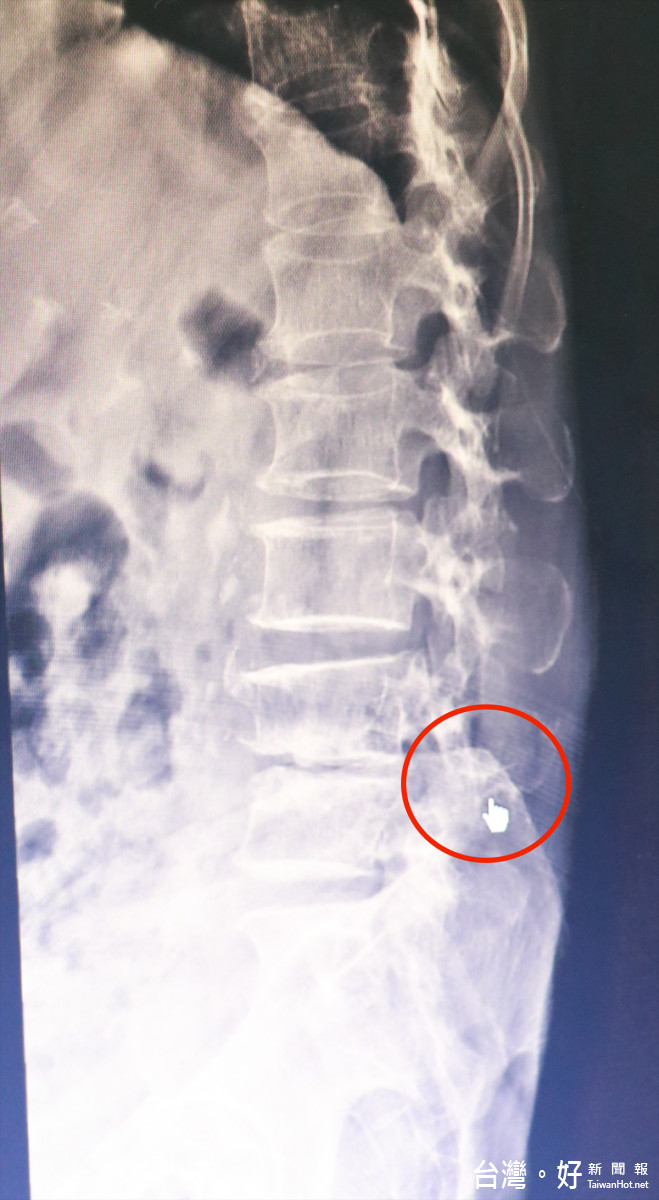

▲蘇阿嬤X光中腰椎壓迫神經處。(圖/七賢脊椎外科醫院提供)

七賢脊椎外科醫院脊椎外科暨疼痛治療中心主任楊子旻說明,該病人經X光及MRI磁振造影確認為腰椎第四及第五節滑脫並壓迫神經,因情況已造成右下肢完全垂足,腳板拖地無法行走,需趕緊手術治療,避免右腳持續萎縮,最後喪失行走功能。經手術後目前病人除復健與定期回診追蹤,平時避免直接過度彎腰、抱重物與姿勢不良造成二度傷害。